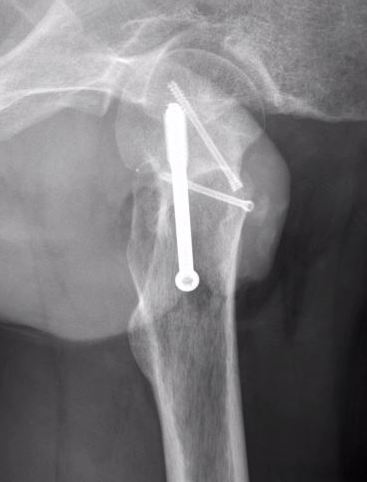

Management

Marginal excision +/- reconstruction

Periosteal chondroma surgery 1Periosteal chondroma 2